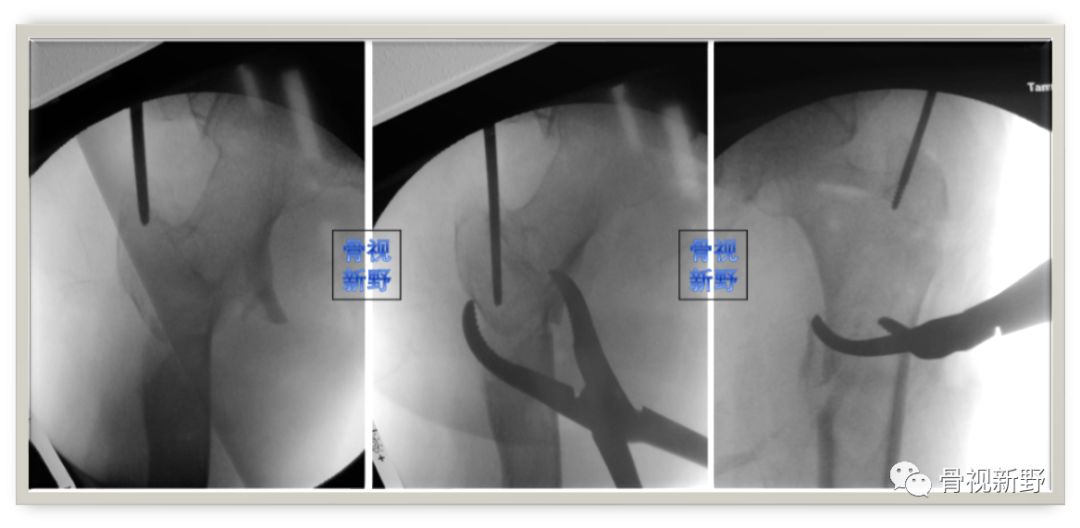

不要对未复位的骨折进行扩髓

由于股骨近端髓腔较宽、骨质较疏松,粗隆间骨折不像长骨干骨折,复位不良是不会通过扩髓或插钉而改善,因此不要对复位不良的粗隆间骨折进行扩髓和插钉。扩髓、插钉前骨折复位啥样、之后还是啥样。

如果骨折不能闭合复位,建议经皮或辅助小切口,通过骨钩、顶棒、复位钳进行复位,然后再进行扩髓。